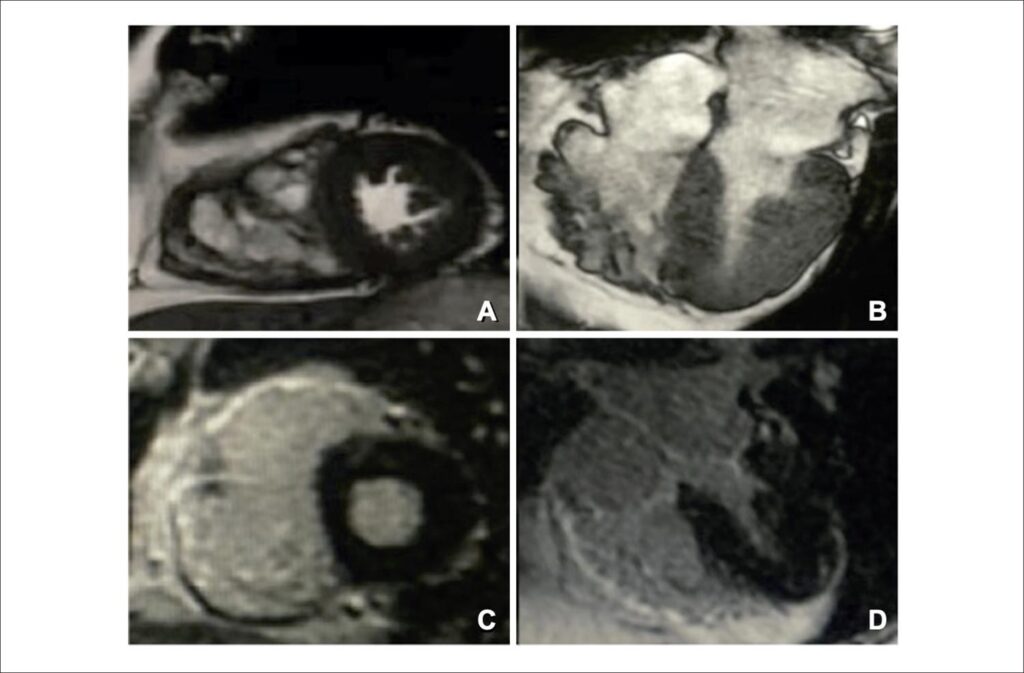

Incidental Finding of Arrhythmogenic Right Ventricular Cardiomyopathy in a 72-Year-Old Man Admitted With Acute Coronary Syndrome

Arrhythmogenic right ventricular cardiomyopathy (ARVC) – also known as arrhythmogenic right ventricular (RV) dysplasia – is a genetic disorder characterized by progressive loss of RV cardiomyocytes, which are replaced with fibrofatty tissue. This replacement may delay intraventricular conduction and contribute to ventricular arrhythmias through a fibrosis-related macro-reentry mechanism. Thus, ARVC is one of the main causes of arrhythmic cardiac arrest in young people and athletes.